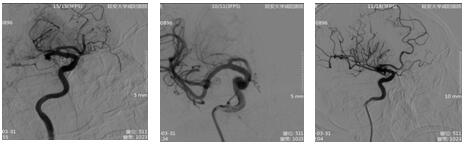

17:21 DSA示:右側大腦中動脈、前動脈閉塞。與患者家屬談話,簽字后立即行中動脈、前動脈取栓術。